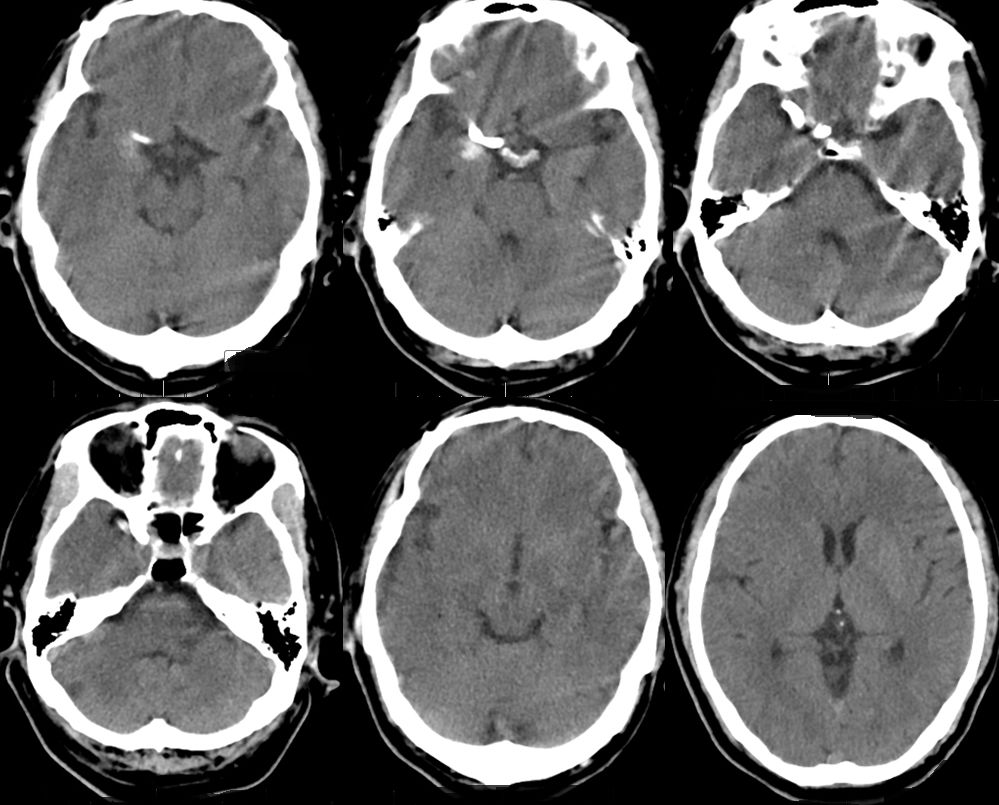

2、Pipeline密网支架释放过程,图像显示支架打开及贴壁良好(图二)。

图二

3、术后支架显影(图三)。

图三

4、术后影像(图四)。

图四